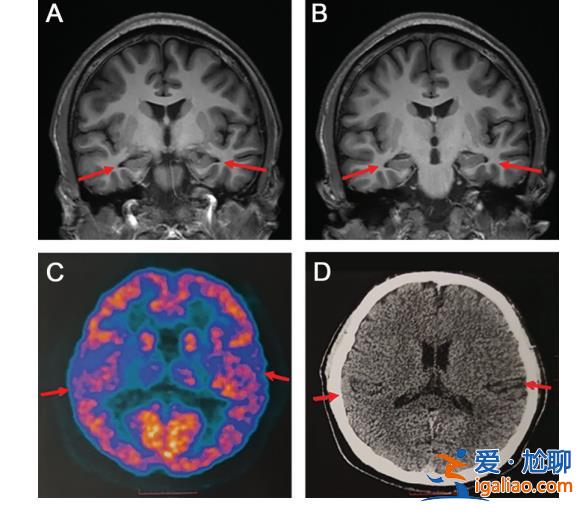

論文稱,醫院為患者做了多種測試,包括目前診斷老年癡呆癥最權威的手段,——腦脊液指標檢測和PET掃描,患者也接受了多種量表測試。掃描圖像顯示患者輕度腦萎縮,部分腦脊液指標異常,最終臨床診斷為阿爾茨海默病。